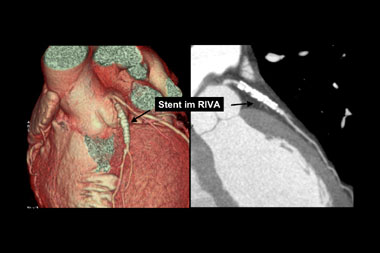

Verkalkungen der Herzkranzgefässe beeinträchtigen aber auch die Darstellung des Lumens in der CT-Angiographie. Bei älteren PatientInnen und solchen mit Diabetes und/oder Niereninsuffizienz, welche ausgeprägte Verkalkungen aufweisen, ist keine schlüssige Beurteilung des Lumens möglich. Zudem kann die EKG-getriggerte Untersuchung bei hoher Herzfrequenz, bei Vorhofflimmern und anderen Rhythmusstörungen, die bei etwa jedem 20. Patienten auftreten, nicht durchgeführt werden. Schliesslich fällt bei Patienten mit schwerer Herzinsuffizienz die Volumenbelastung durch das Kontrastmittel ins Gewicht. Auch durch Stents verursachte Artefakte stellen ein diagnostisches Problem dar (Abbildung 3). Obschon die neuesten CT-Geräte sehr genau die Stentlänge und den Durchmesser erfassen können, ist eine sichere Beurteilung des Lumens in vielen Fällen noch nicht möglich. Da bei der koronaren Herzkrankheit die Frage nach einer Intervention im Vordergrund steht, sei es eine kathetertechnische Stent-Implantation oder eine Bypass-Operation, ist die Erfassung von Koronarstenosen das Hauptziel. Entsprechend ist diese Einschränkung der Aussagekraft der computertomographischen Koronarangiographie durch Gefässwandverkalkungen ein grosser Nachteil dieser Methode. Zusammenfassend ist daher ist der negativ prädiktive Wert der computertomographischen Koronarangiographie sehr hoch. Der positive prädiktive Wert behandlungsbedürftiger Koronarstenosen ist aber beschränkt.

Abbildung 3: Stents stellen ebenfalls eine Herausforderung dar. Zwar können Stents sehr gut v.a. dreidimensional dargestellt werden (links), doch die Beurteilung des Lumens ist häufig beeinträchtigt.